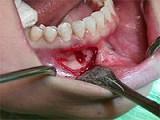

问题 组图为牙瘤的外观及X?线表现,有关此病的描述错误的是()

选项 A.多见青年人 B.生长缓慢,早期无自觉症状 C.由牙胚组织异常发育增生而形成 D.X?线可见类似发育不全牙的影像 E.绝大多数为恶性

答案 E